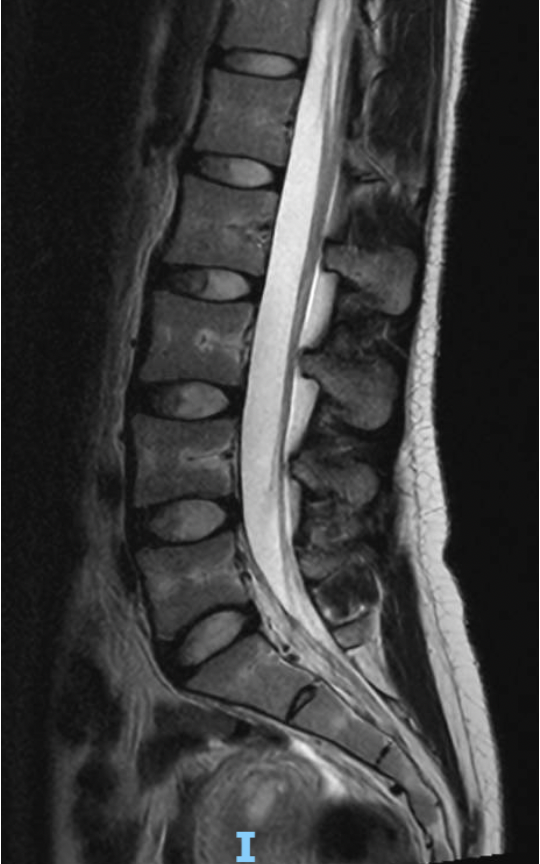

MRI scan of the human lower back spine showing vertebrae, spinal cord, and surrounding tissues in black, white, and gray shades.

A lumbar MRI shows the bones (vertebrae) stacked on top of each other with smooth alignment. Between each bone is a disc, which acts as a cushion and allows the spine to move. On a normal MRI, the discs appear well hydrated and maintain their height.

The spinal canal, which protects the nerves, appears open with adequate space.

The nerves travel from the spinal canal into the legs through small openings called foramina. On a normal MRI, the nerves have enough room and are not compressed by discs, bone spurs, or thickened ligaments.